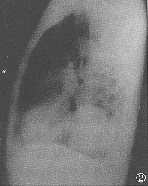

肺炎性假瘤肺炎性假瘤可發生在兩肺的任何部位。本組右上肺(12/20)多於左上肺(2/10)的假瘤,多位於下葉背段和內後基底段。球型瘤體一般邊緣光滑銳利,直徑多在1~4 cm,密度比較均勻,周圍肺野清晰。團塊樣的瘤體一般境界不清,邊緣模糊。部分病灶密度濃淡不勻,如多次並發急性炎症可造成“瘤”影擴大,在其周圍恰似炎性浸潤的片狀影。因此假瘤邊緣清楚與否取決於腫塊周圍的病理變化。境界面清楚者,瘤體周圍一般有假性包膜,若病灶處於急性階段時,假瘤周圍顯示炎性,滲出在瘤體周圍多呈模糊影亦無假包膜形成。

肺炎性假瘤X線表現:假瘤可發生在肺的任何部位,球型瘤體由於有較完整的假性包膜,因此輪廓清楚,邊緣光滑,周圍肺野清晰。團塊狀的瘤體由於假包膜不完整,一般境界不清,邊緣模糊,部分病灶密度濃淡不勻,如多次並發急性炎症,可造成“瘤”影擴大,在其周圍恰似炎性浸潤的片狀影。崔氏報導的“桃尖征”本組出現率不高,其病理基礎可能是一種腫瘤包膜粘連的徵象;CT表觀:CT圖像把假瘤與肺的界面,特別是假瘤的邊緣、密度、空洞、長毛刺影與胸膜粘連等顯示得非常清楚。本文36例胸部平片僅2例見有空洞影,而25例CT掃描發現9例小空洞,這種空洞可以單發也可多發。少數瘤體切開時可見膿性物。假瘤邊緣可以不規則或呈鋸齒樣,也可呈分葉狀。CT肺窗圖像上,腫瘤邊緣可清楚地顯示炎性滲出影。長毛刺、與胸膜緊貼或有粘連帶等對本病的診斷具有一定的意義。假瘤術前診斷的主要方法靠X線、CT檢查。胸部正側位相能顯示假瘤的全貌,CT掃描有助於顯示瘤體內部結構(即空洞、鈣化、毛刺、血管、纖維索條影等)。